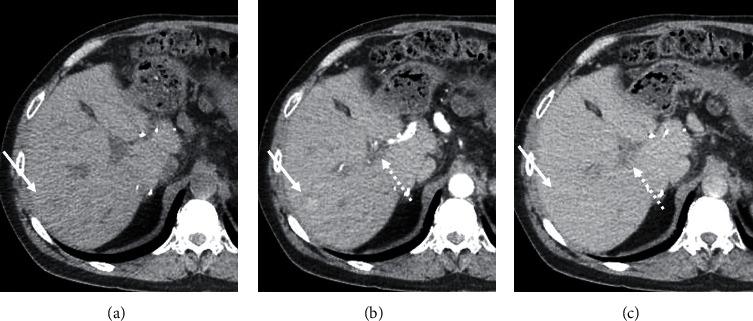

肝移植(LT)后,受者会像其他患者一样出现良性和恶性肝脏肿块。因肝细胞癌(HCC)接受移植的患者需进行监测成像,成像中发现的任何新肿块都必须仔细评估以排除复发性癌症。局灶性结节性增生(FNH)是一种肝脏良性肿瘤,最常见于女性,很少有症状。将FNH与更严重的病因(如复发性HCC和其他恶性肿瘤)区分开来很重要,因为治疗方法差异很大。迄今为止,关于肝移植受者发生FNH的报道非常少。我们报告一例有类癌病史的患者,因HCC接受了LT。移植后数年,该患者在成像中发现肝脏肿块,具有HCC的典型特征。肝脏活检显示意外诊断为FNH。这一发现避免了对HCC进行不必要的治疗,HCC治疗会带来并发症,尤其是在移植后。我们介绍了我们的诊断方法,讨论了FNH的临床病理和成像表现,并回顾了移植后FNH的相关文献。